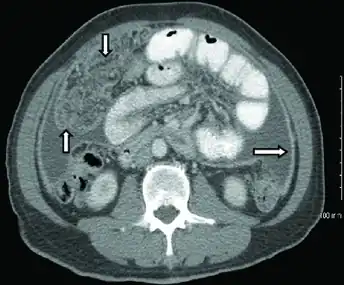

Gastrointestinal

Abdominal infections include gastrointestinal tuberculosis (which is important to distinguish from Crohn's disease, since immunosuppressive therapy used for the latter can lead to dissemination), tuberculous peritonitis, and genitourinary tuberculosis.[4]